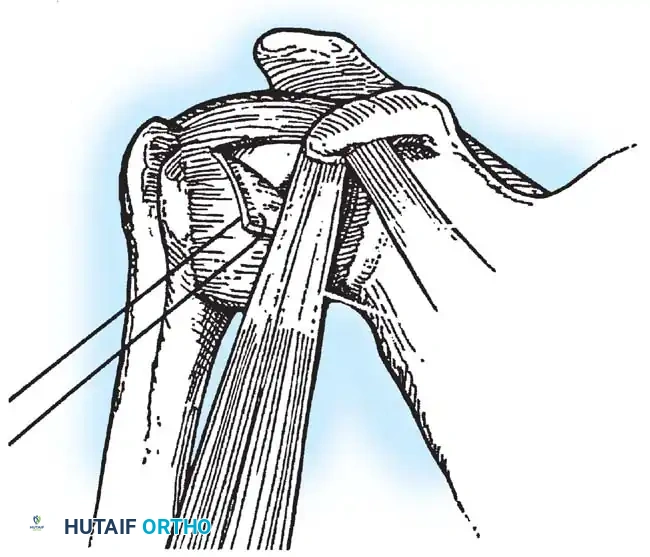

Glenoid Preparation and Labral Repair

The essential step in restoring stability is the anatomical reduction of the capsulolabral complex to a bleeding bone bed on the anterior glenoid rim.

- Debridement: The anterior glenoid neck is decorticated using a motorized burr, rasp, or osteotome to create a bleeding cancellous bed. This promotes robust biological healing of the repaired labrum.

- Mobilization: The scarred, medially displaced labrum (ALPSA lesion) must be fully mobilized using a periosteal elevator until the subscapularis muscle belly is visible anteriorly. The tissue must float freely to be shifted superiorly and laterally.

- Anchor Placement: Suture anchors (typically 3 to 4) are placed along the articular margin of the anteroinferior glenoid (from the 5:30 to 3:00 positions for a right shoulder). Anchors must be inserted at a 45-degree angle to the articular surface to maximize pullout strength and avoid joint penetration.